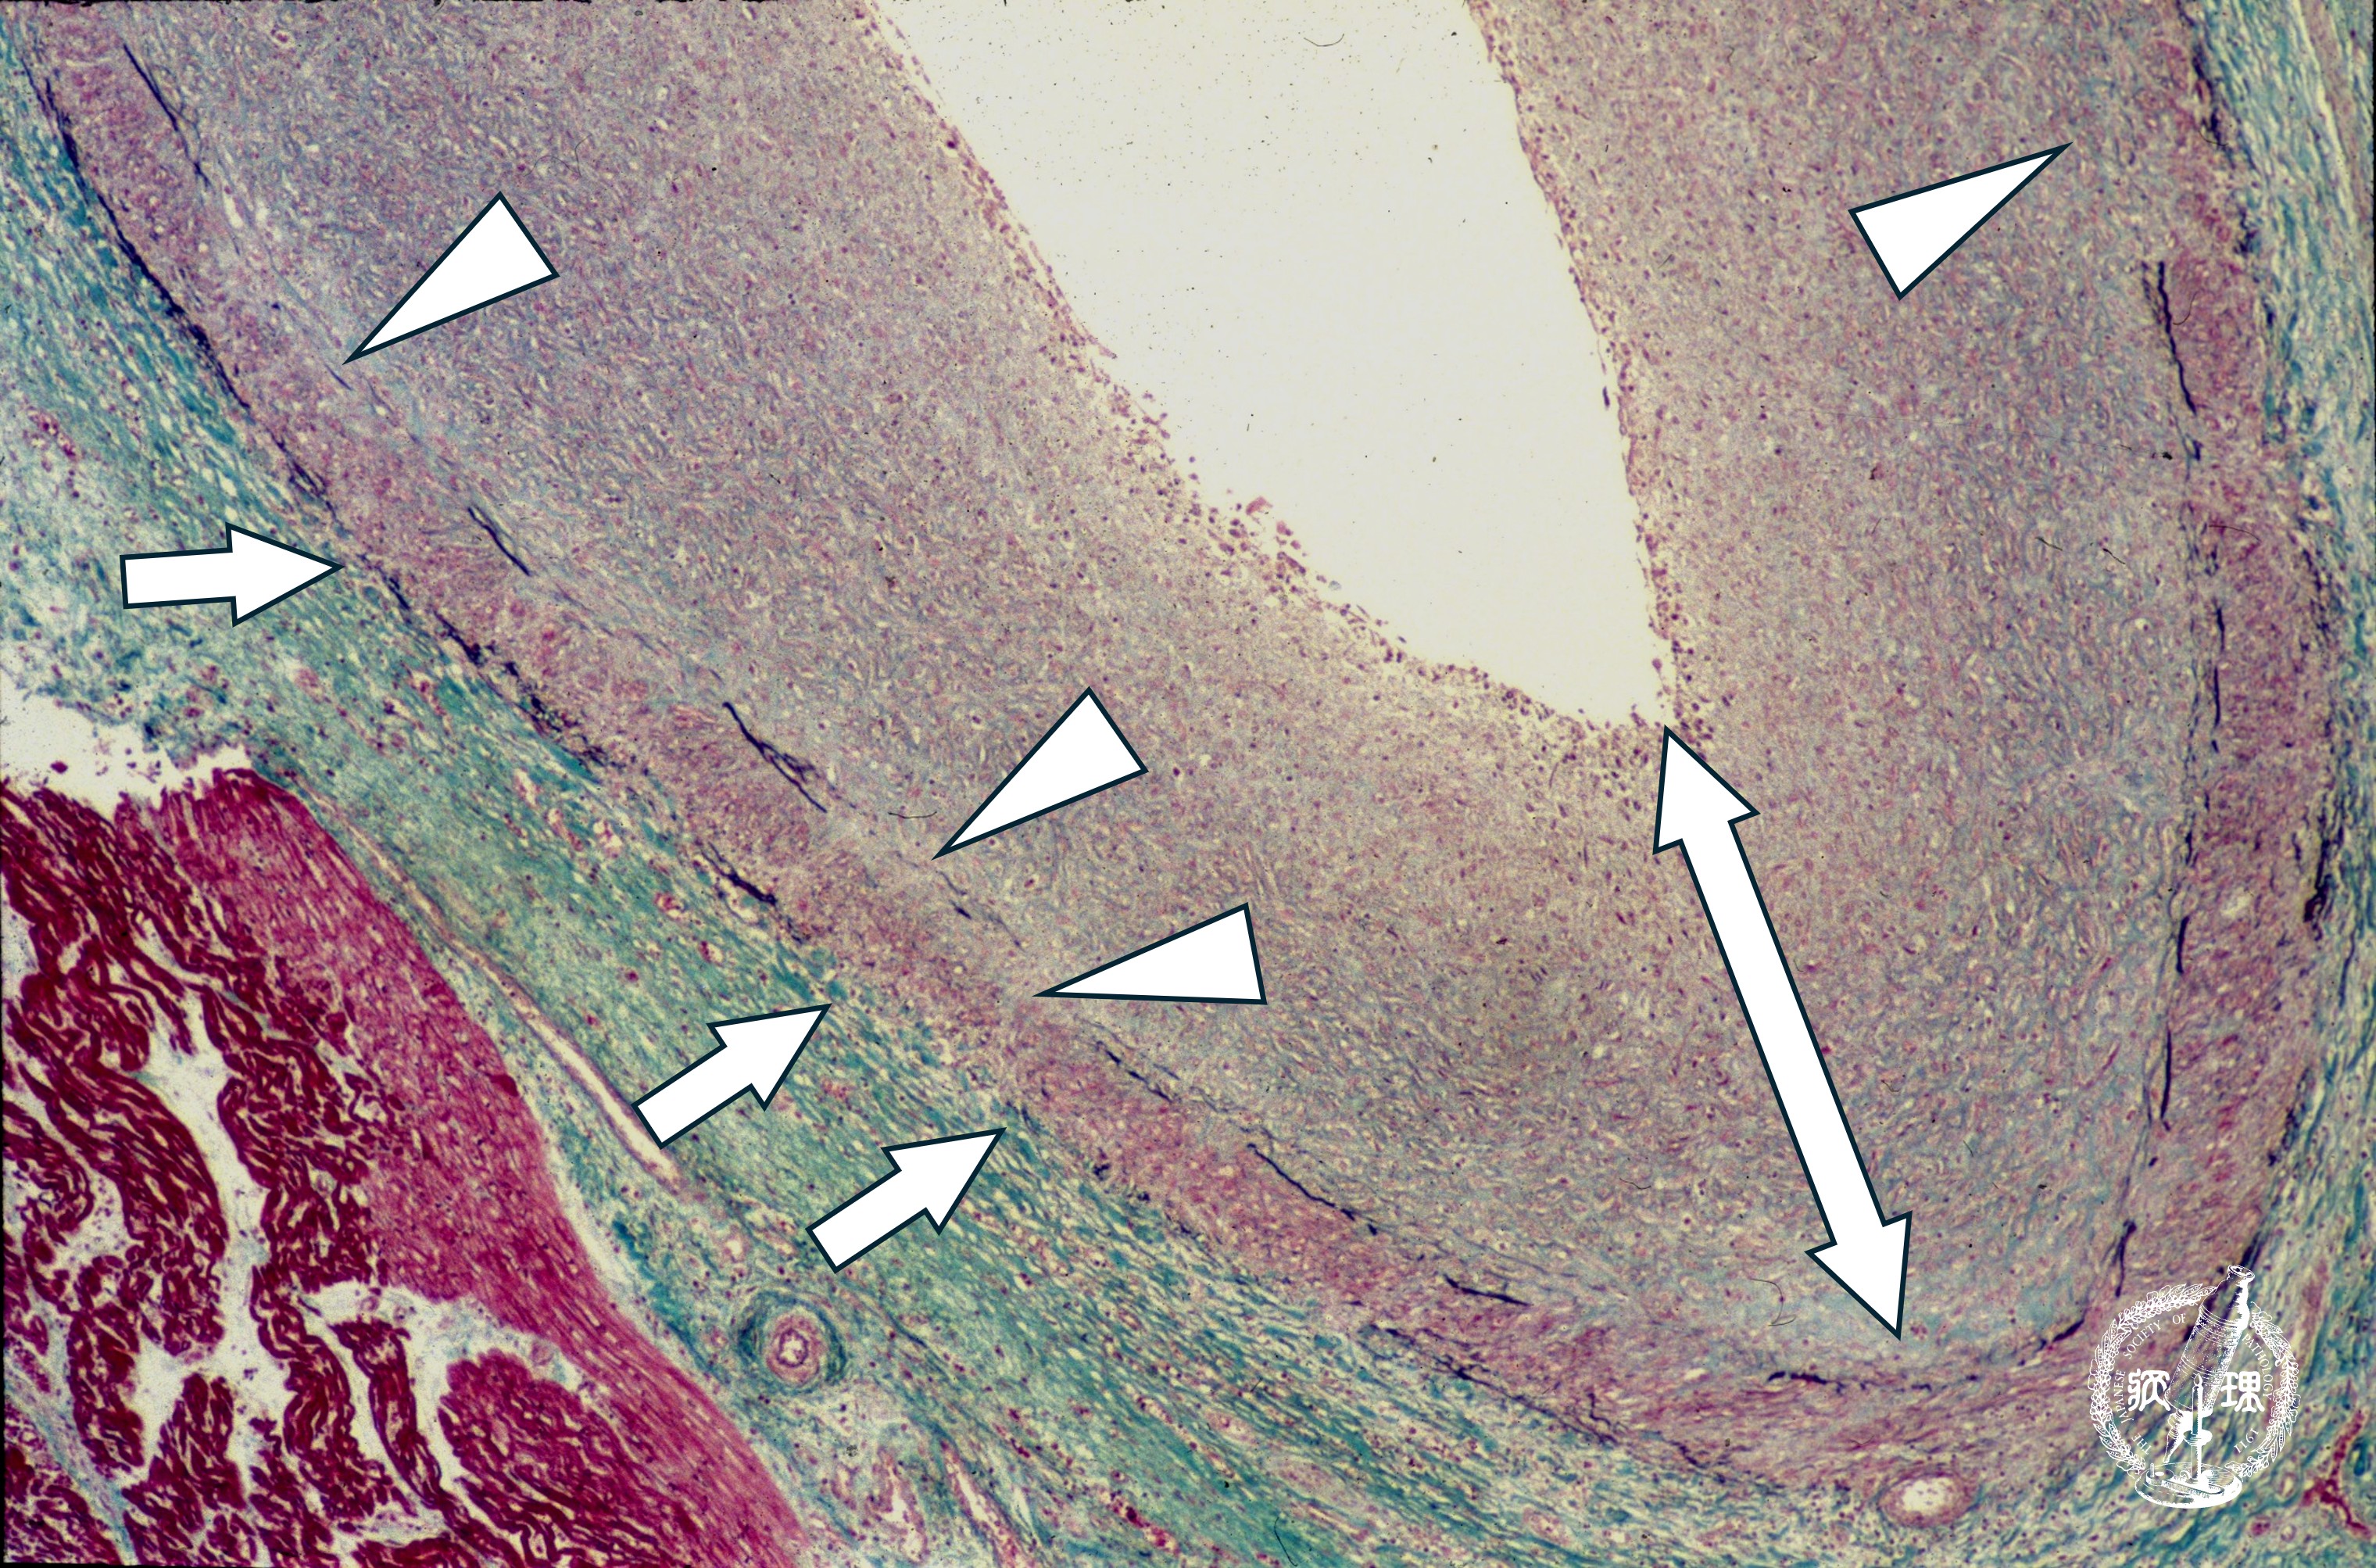

ミクロ像 (Elastica-Masson染色): 外弾性板の断裂(矢印)、内弾性板の断裂・消失(矢頭)とともに内膜の著明な肥厚(両矢印)を認める。